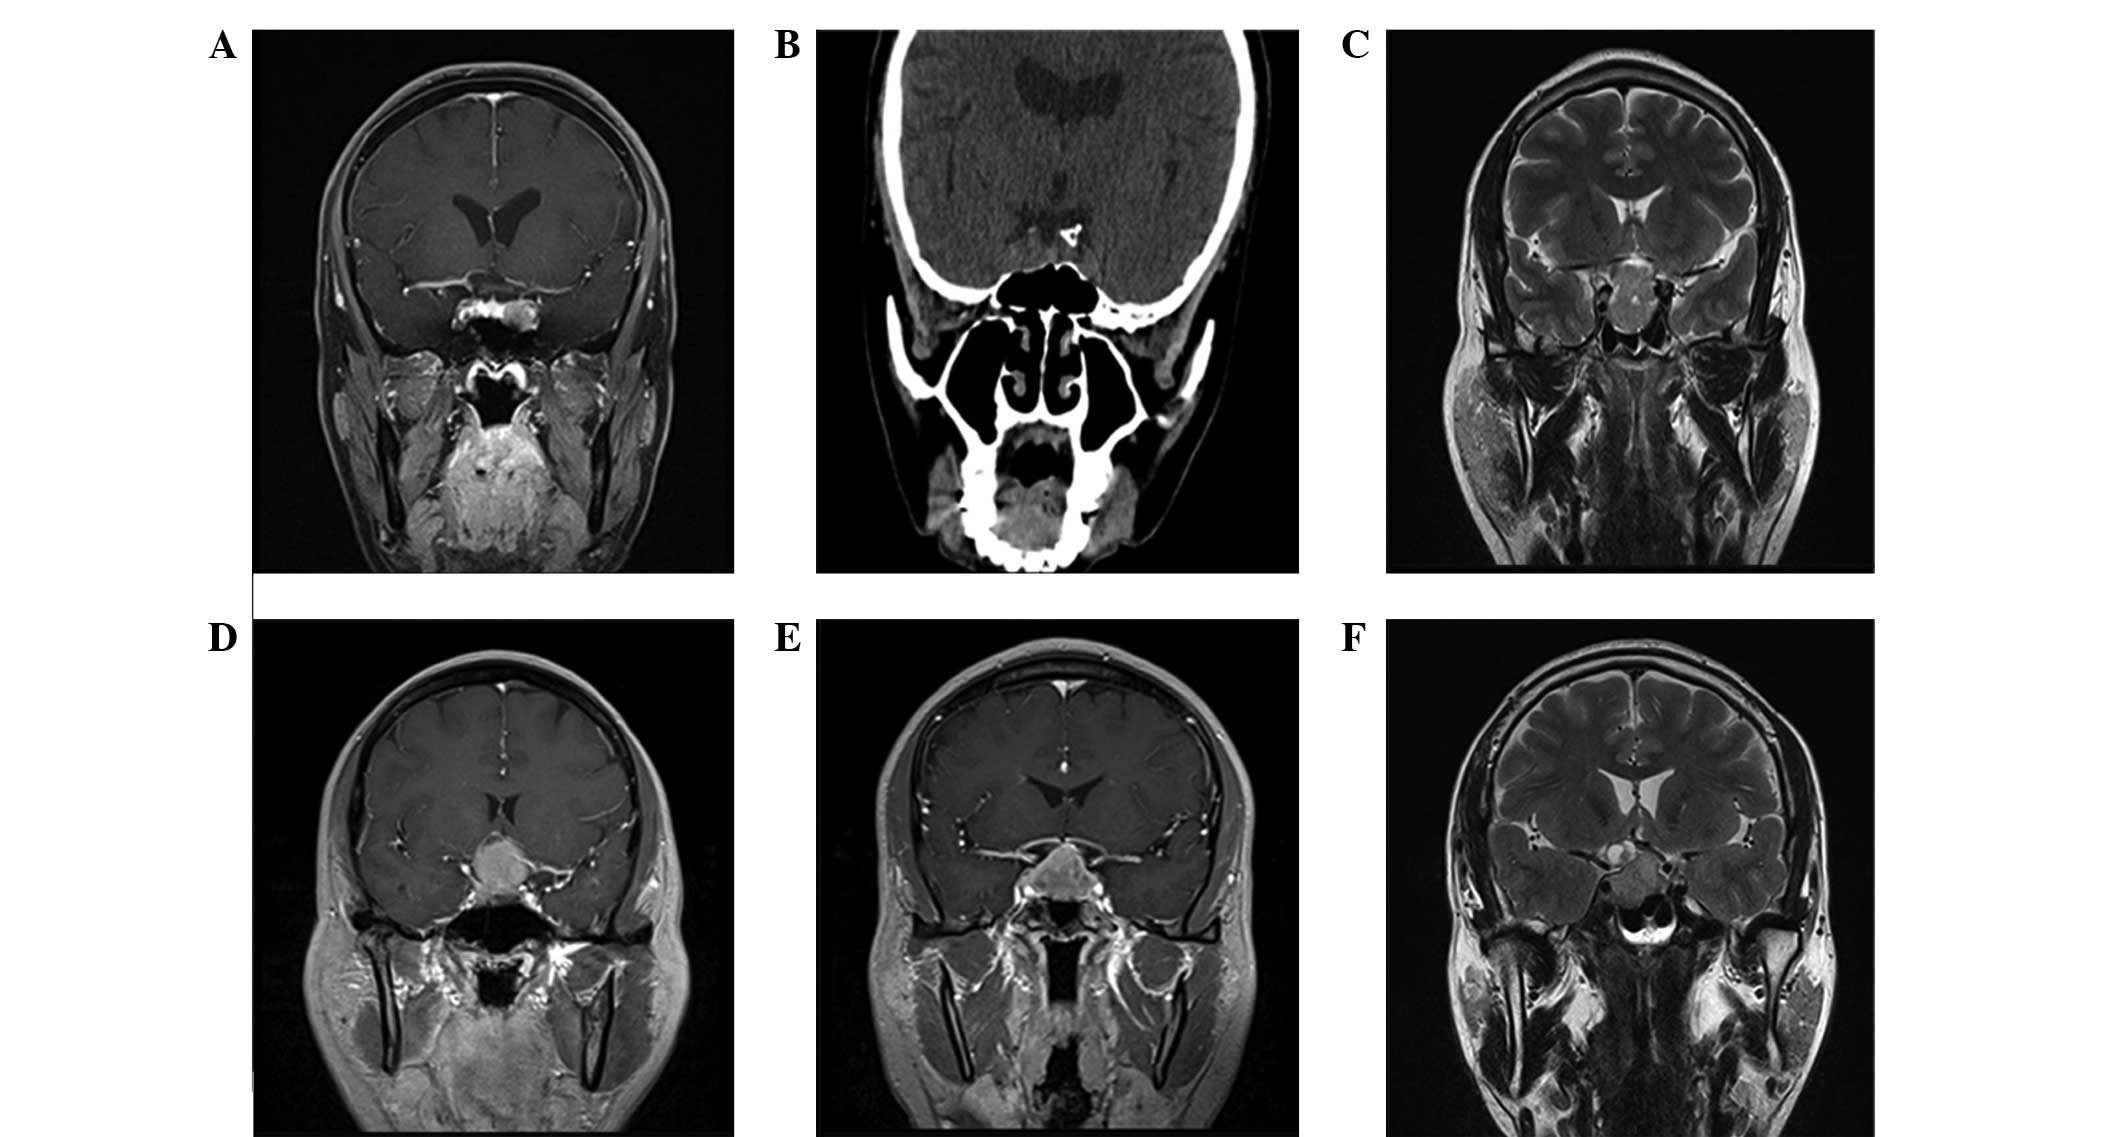

Total resection surgery was achieved through the nose and sphenoid sinus in 64 patients, and 25 patients underwent subtotal resection or substantial removal of the tumor, leaving a small area of residual tumor or tumor capsule. Craniotomy was conducted in 13 patients, which were cases where the tumors were growing invasively with suprasellar extension and it was observed during surgery that the internal carotid artery was surrounded by optic chiasm that had unclear boundaries with brain tissue. MRI results of the head and coronal CT scans are presented in Fig. 1. The surgical observations of patients with and without bromocriptine treatment are presented in Table I. Significant differences (P<0.05) in the tumor texture and the frequency of hard and tough capsules and pituitary stalk adhesions were detected between the two groups.

Figure 1.

Magnetic resonance imaging of the head and coronal computed tomography scanning used to diagnose prolactinoma. Patients were diagnosed with a pituitary tumor when an abnormal signal was exhibited by the pituitary gland. Tumor volumes are (A) 15×16×20 mm, (B) 14×16×27 mm, (C) 29×36×19 mm, (D) 23×31×26 mm, (E) 22×25×32 mm and (F) 19×11×22 mm.